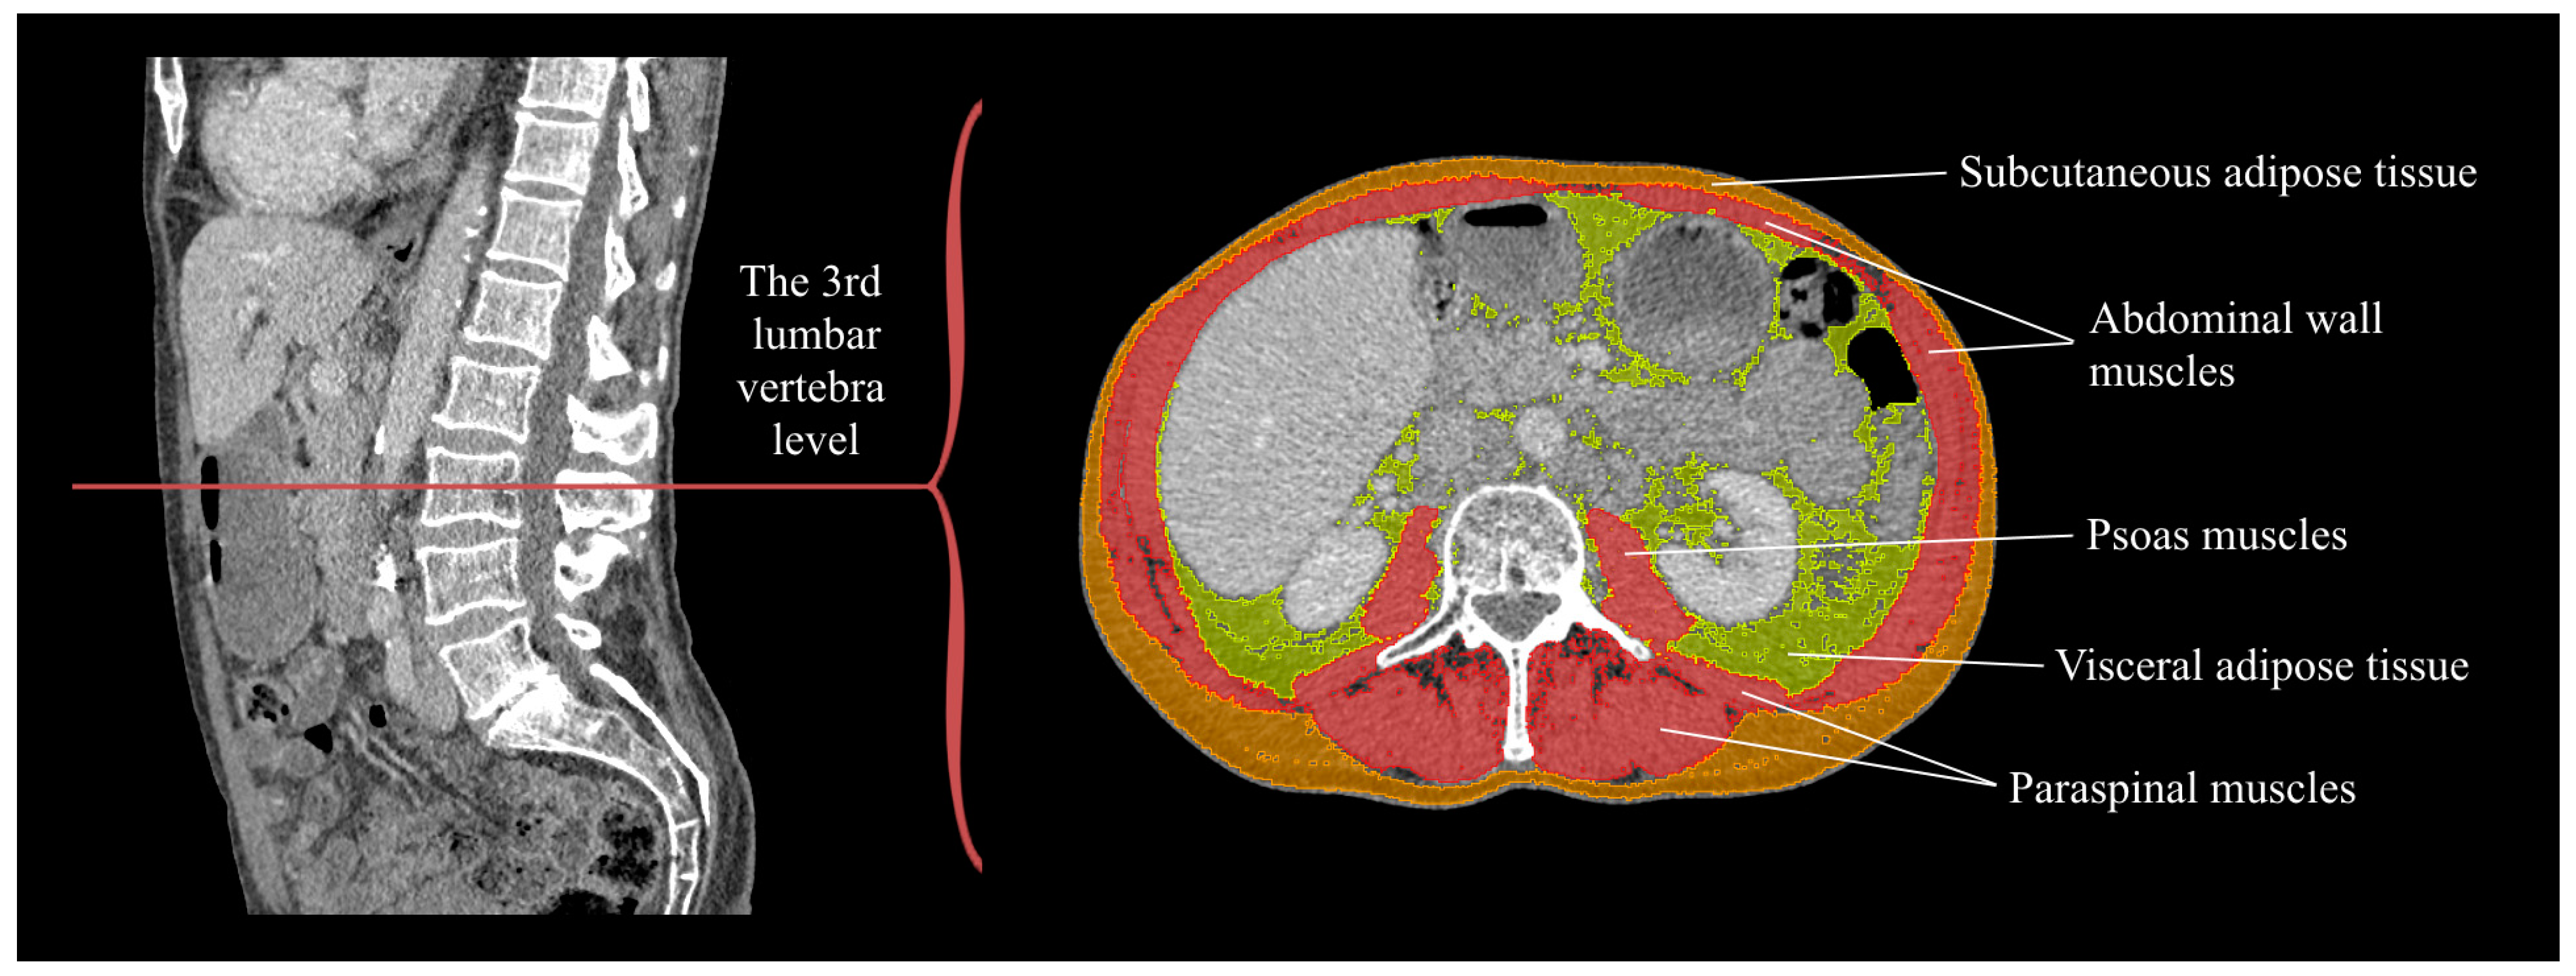

2.3. Body Composition Analysis

- Tolonen, A.; Pakarinen, T.; Sassi, A.; Kyttä, J.; Cancino, W.; Rinta-Kiikka, I.; Pertuz, S.; Arponen, O. Methodology, Clinical Applications, and Future Directions of Body Composition Analysis Using Computed Tomography (CT) Images: A Review. Eur. J. Radiol. 2021, 145, 109943. [Google Scholar] [CrossRef]